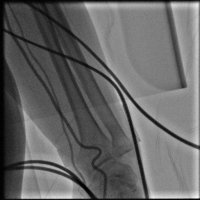

Başka merkezde CTO işlemine alınıp başarısız olup kliniğimize başvuran hastaya RCA uzun ve tandem CTO lezyonları özel mikro kateter ve teller ile geçilerek balon ve stent işlemleri başarıyla sonuçlandı.